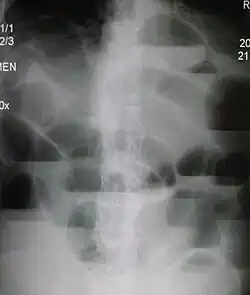

Upright abdominal X-ray of a person with a large bowel obstruction showing multiple air fluid levels and dilated loops of bowel